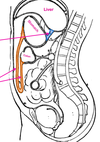

fill in labels

label the gastrophrenic ligament and the splenorenal ligament: